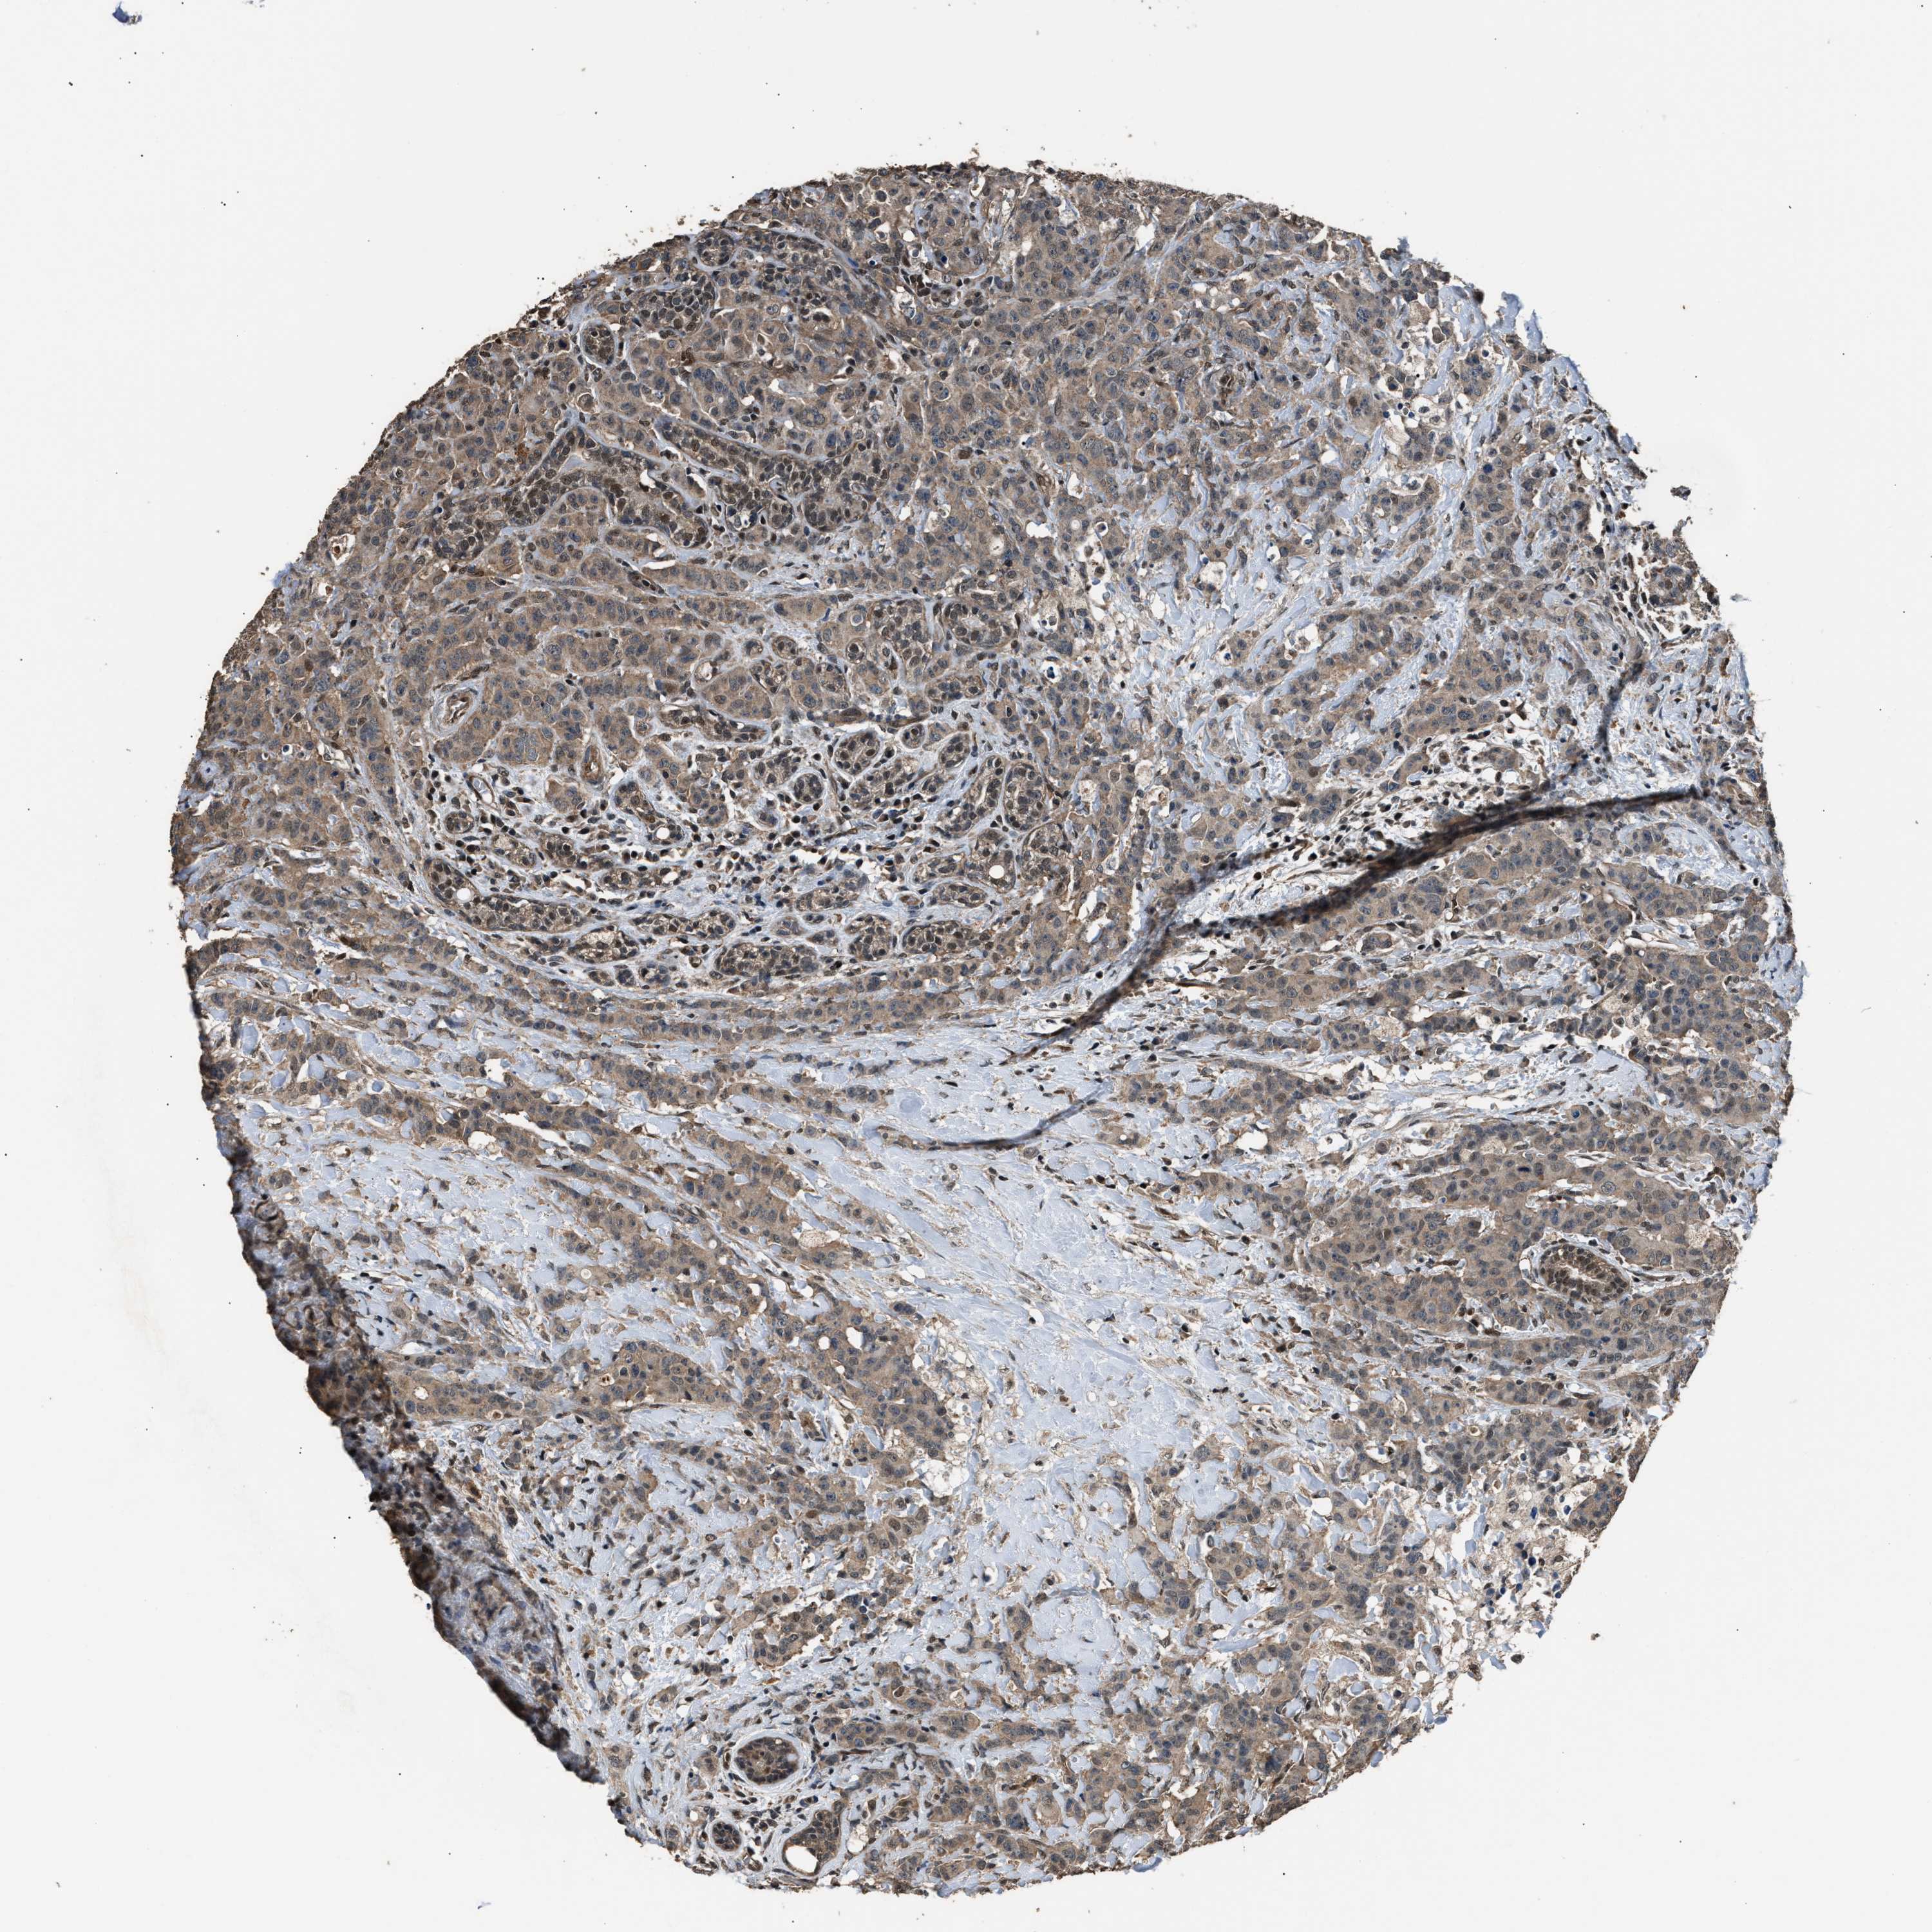

CANCER BREAST CANCER Show tissue menu

BRCA TCGA BRCA VALIDATION PROTEIN EXPRESSION